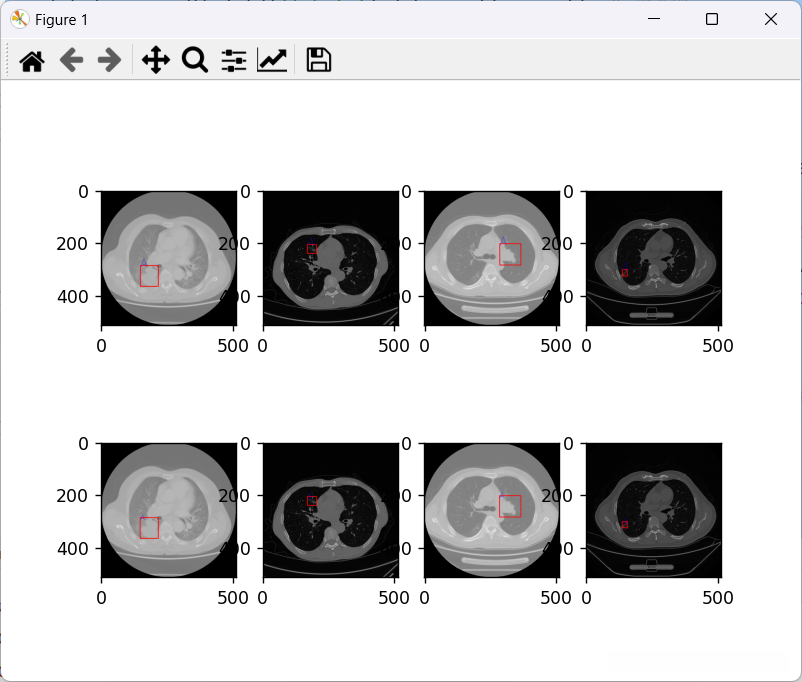

5.2 结果展示

这里呈现的是(训练数据集合)通过以下链接可获得:

第一行为truth,第二行为prediction

该测试集在测试集中的表现较为突出,在评估指标中呈现出良好的效果。

可能因为数据的原因吧,iou虽然不高,但是在testSet 的表现也比较好